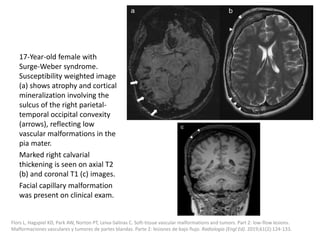

MRI findings are also subtle, with skin thickening

and occasional increased subcutaneous thickness

and faint focal T2 hyperintensity and contrast

enhancement.

Fayad LM, Hazirolan T, Bluemke D, Mitchell S. Vascular malformations in the extremities: emphasis on MR imaging features that guide

treatment options. Skeletal Radiol. 2006;35: 127-37.

Moukaddam H, Pollak J, Haims AH. MRI characteristics and classification of peripheral vascular malformations and tumors. Skeletal Radiol.

2009;38:535-47.

Restrepo R. Multimodality imaging of vascular anomalies. Pediatr Radiol. 2013;43 Suppl. 1:S141-54.

Treatment

Laser therapy is the standard treatment.

Surgical procedure may be considered when